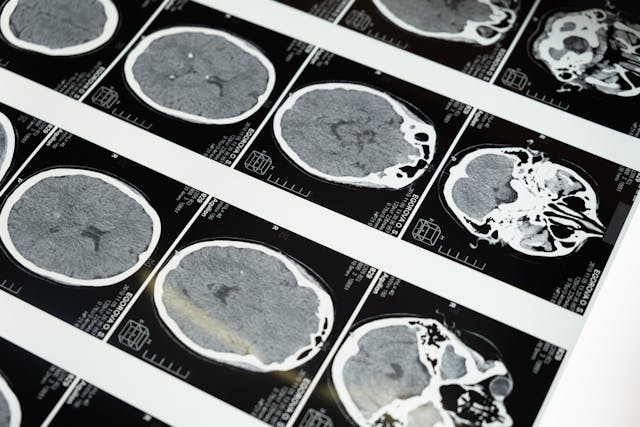

Luke said the diagnosis sent him inward at once. “I thought I was going to die,” he recalled after doctors told him he might have only days left without emergency surgery. That response makes complete sense. Patients often spend years fearing they are being ignored, then face the opposite shock in a single appointment. One day, they are being reassured. The next day, they hear words like brain tumor, emergency surgery, and life-threatening pressure. That violent change in perspective often breaks people long before treatment begins. A brain scan does not simply reveal a mass. It can also demolish the emotional scaffolding that helped someone cope during the uncertain years. MRI and CT scans play a central role in suspected brain tumor diagnosis because symptoms alone often overlap with common disorders.

NICE guidance on brain tumors in adults covers the diagnosis and management of primary brain tumors and brain metastases, while NICE suspected cancer guidance supports primary care decisions about investigation and referral. Cancer Research UK says urgent referral for brain imaging may be considered when clinicians suspect a worsening problem involving the brain or central nervous system. The NHS also tells patients to seek assessment for headaches that are different from usual or keep worsening. Those recommendations are not meant to send every person with a headache into the scanner. They exist because imaging becomes decisive once the wider clinical picture starts to change. The difficulty is that people often normalize a slow deterioration. They adapt to pain, cancel plans, and sleep more.